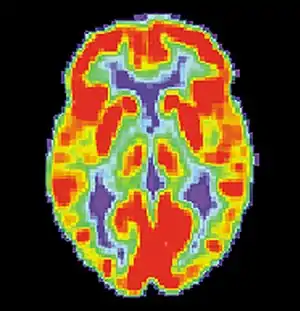

PET scan of a healthy brain - Image courtesy of US National Institute on Aging Alzheimer's Disease Education and Referral Center

PET scan of a healthy brain - Image courtesy of US National Institute on Aging Alzheimer's Disease Education and Referral Center PET scan of brain with AD - Image courtesy of US National Institute on Aging Alzheimer's Disease Education and Referral Center

Alzheimer's disease (AD) is a progressive, degenerative and fatal brain disease, in which cell to cell connections in the brain are lost. Alzheimer's disease is the most common form of dementia.[2] Globally approximately 1–5% of the population is affected by Alzheimer's disease.[3] Women are disproportionately affected by Alzheimer's disease. The evidence suggests that women with AD display more severe cognitive impairment relative to age-matched males with AD, as well as a more rapid rate of cognitive decline.[4]